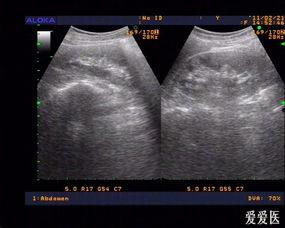

当阑尾炎发作时,手术切除阑尾成了最常见的治疗方法。那么,割掉的阑尾长什么样呢?让我们一起来看看这些真实的阑尾图片。

1. 红肿的阑尾

在阑尾炎早期,阑尾会出现红肿现象。这时,阑尾的表面看起来像是一根被吹胀的气球,颜色鲜红,质地坚硬。